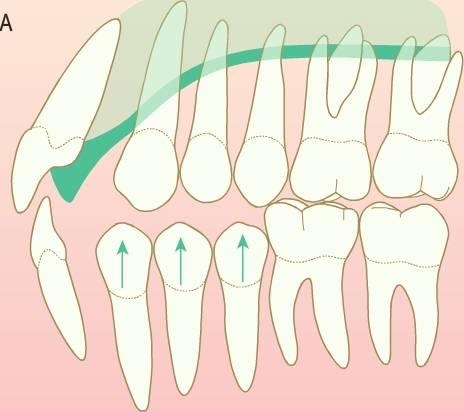

Siempre que se produzca la pérdida prematura de un segundo molar temporal, antes o después de la erupción del primer molar permanente, se producirá alguna pérdida de longitud de arcada provocada por el desplazamiento mesial del molar permanente (fig. 11.3).

El mantenimiento del espacio resulta crítico en niños que tienen una longitud de arcada normal y pierden un molar temporal. Cualquier pérdida de espacio en estos niños provocará el apiñamiento de los dientes permanentes.

En las zonas en las que ya se haya producido la pérdida de espacio se precisa recuperarlo y posteriormente colocar un mantenedor de espacio.